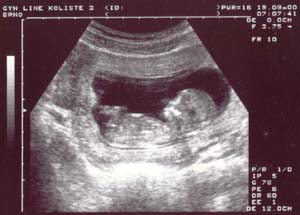

14. týden: páteř plodu

14.týden